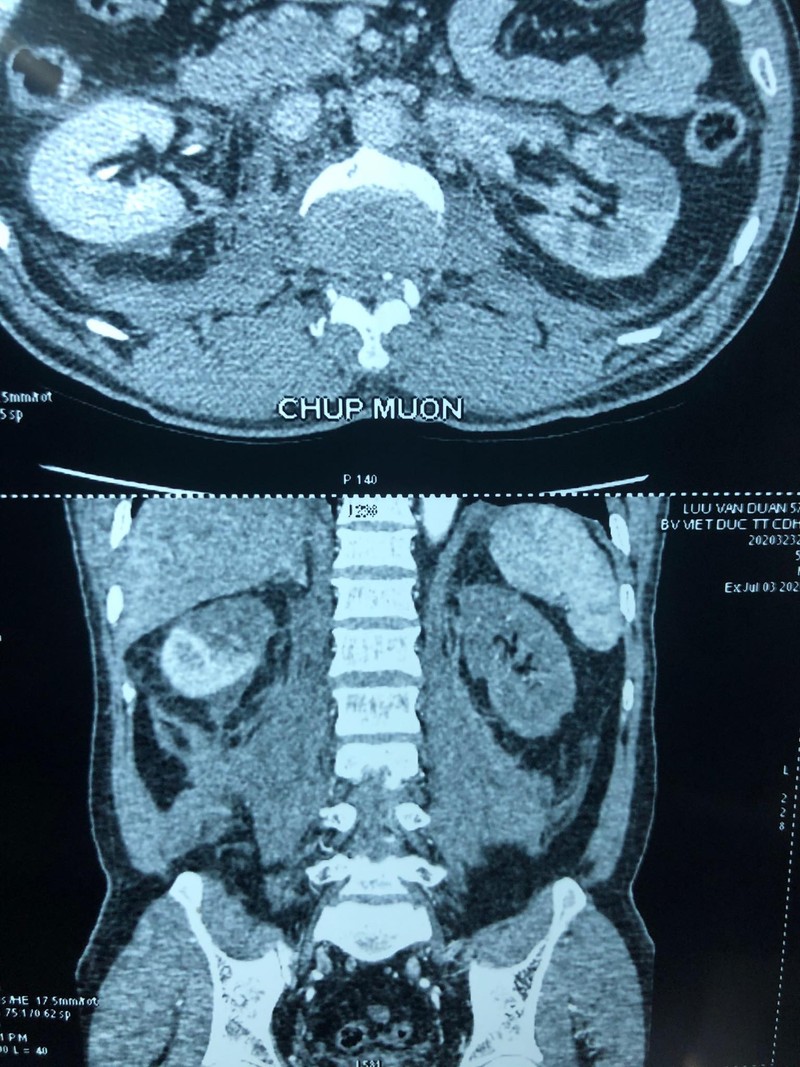

Với kết quả chụp chiếu tại bệnh viện, các bác sĩ phát hiện thận bên phải của nạn nhân có một huyết khối động mạch cực trên khiến phần cấp máu cho cực trên bị mất, thận bên trái thiếu máu hoàn toàn, chức năng thận giảm, có biểu hiện suy thận.

Ngay lập tức, bệnh nhân đã được hội chẩn liên chuyên khoa Tiết niệu – Tim mạch – Ghép tạng. Các bác sĩ đã quyết định mổ cấp cứu để thăm dò cố gắng cứu sống thận bên trái cho anh D., tránh suy thận do đa chấn thương.

Thông thường, với những tổn thương tắc động mạch thận, phẫu thuật sớm từ 6-8 tiếng sau tai nạn mới có thể cứu được thận. Tuy nhiên ở trường hợp anh D. khi được chuyển vào phòng mổ tổn thương tắc động mạch thận của bệnh nhân đã bước sang giờ thứ 24 - quá :thời gian vàng: cho một ca ghép thận tự thân.